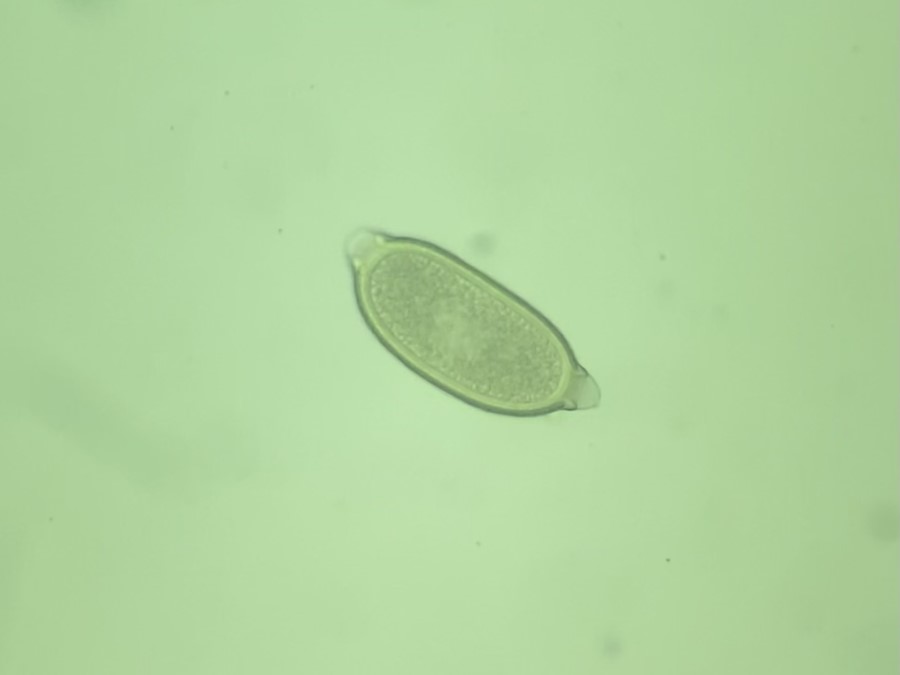

Vista 2 Nematodo gastrointestinal

Nematodo gastrointestinal

Fuente: R Molnár, C Connor - Algunos derechos reservados (CC BY-NC 4.0)

Datos taxonómicos

Género:

Capillaria

Especie:

spp

Nombre común: